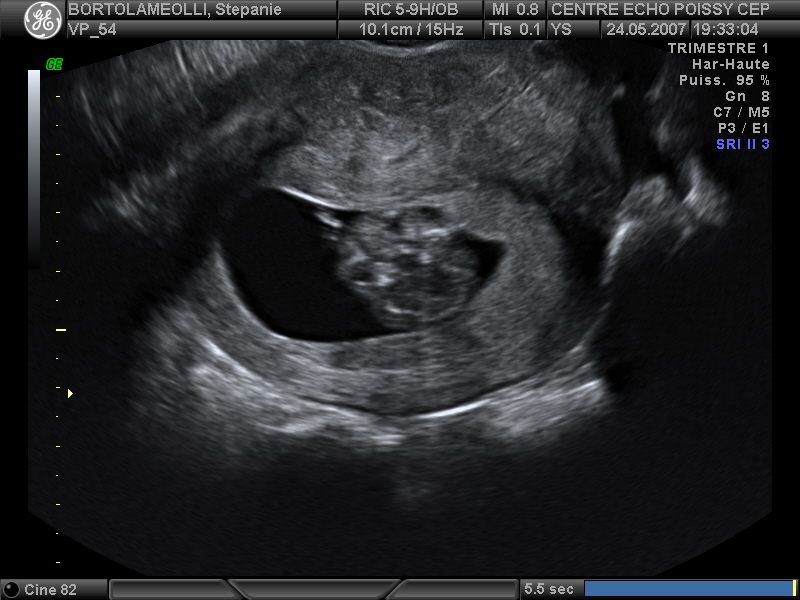

Echographies

Mai 2007